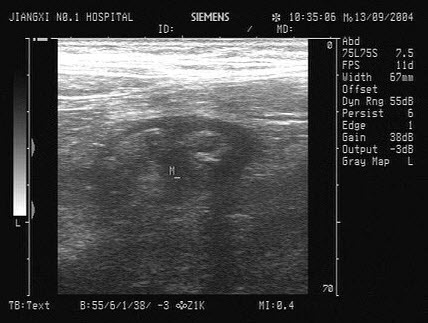

13、单项选择题

患者,右下腹压痛,体温38.5℃。根据右下腹声像图表现,诊断是()

A.腹膜炎

B.结肠癌

C.阑尾脓肿

D.单纯性阑尾炎

E.腹水

14、单项选择题 人体组织和体液中,哪一种最少引起声衰减()